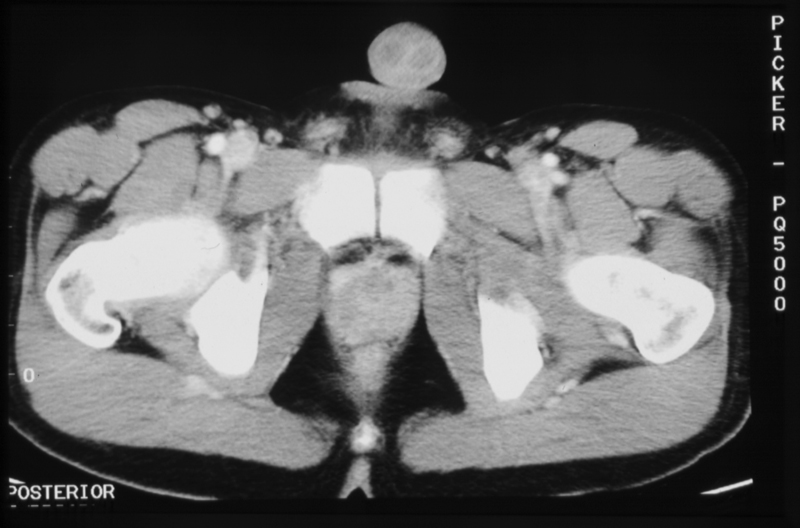

The Structural Basis of Medical Practice

College of Medicine